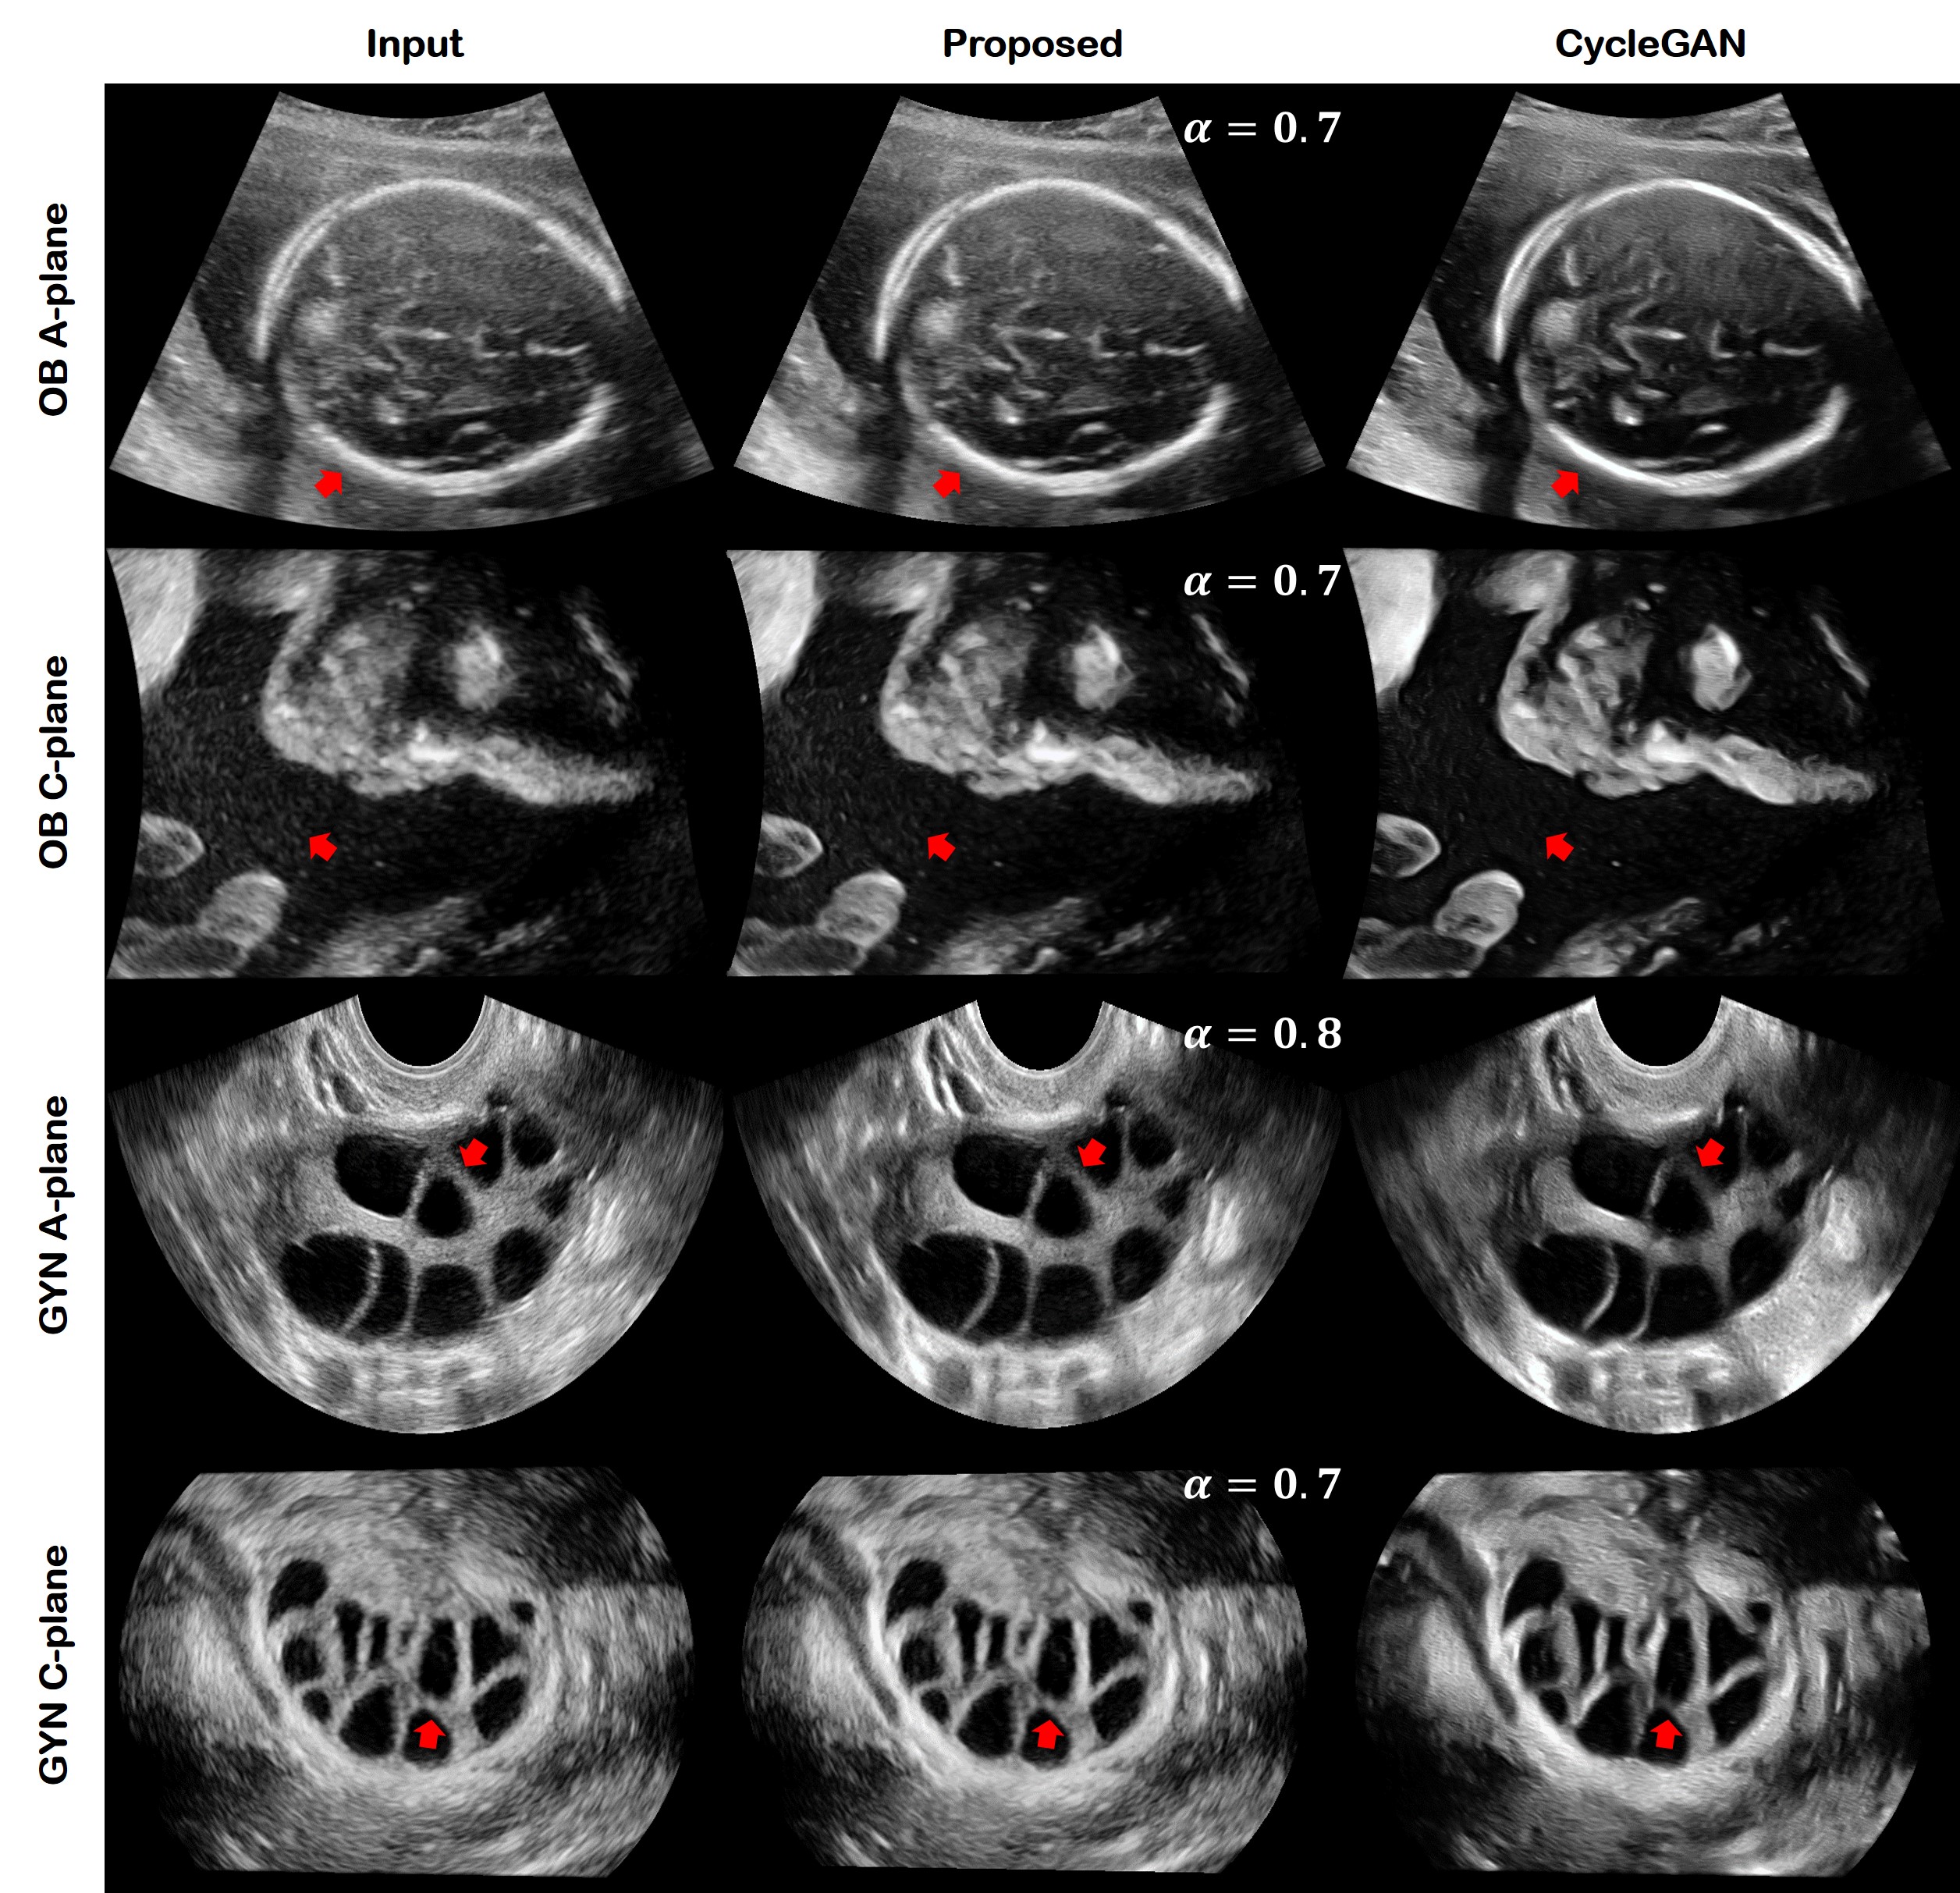

Fig. 8: The comparison result between the proposed method and standard CycleGAN. The first and second rows are obstetric A- and C- planes. The third and fourth rows are gynecology A- and C- planes. The first columns denotes the input image. The second and third columns are the result from the proposed method and the CycleGAN, respectively. The differences seen at the red arrows are discussed in the main text.

Specifically, the comparison results are shown in Fig. 8. We visualized OB A-, C- planes and GYN A-, C- planes. The first column is the input image and the second, third column are the results of the proposed method and CycleGAN. Both the proposed method and the CycleGAN results show an improvement in image quality such as noise reduction and contrast enhancement. However, as can be seen in the first row where the red arrow is pointing, the bone is emphasized too much by CycleGAN. It leads to misinterpretations in the case of biparietal diameter assessment. In the second row, the red arrow points to the float in the amniotic fluid. It contains important information to interpret the status of the fetus. For example, the movement of the particles can be crucial criteria to diagnose the digestive system disorders. However, the CycleGAN recognized this as a noise and suppressed it. On the other hand, the proposed method retains it with high contrast, in particular it can be more visible by controlling the α𝛼\alpha value. In the third and fourth rows, the red arrow points to the ovarian structure, which can determine the status of the follicle. Since the 2-D quality emphasizes the contrast too much, it sometimes suppresses the weak signal. As you can see in the third and fourth rows, the structure becomes invisible in the CycleGAN result. On the contrary, the proposed method shows sharp boundaries compared to the input image.